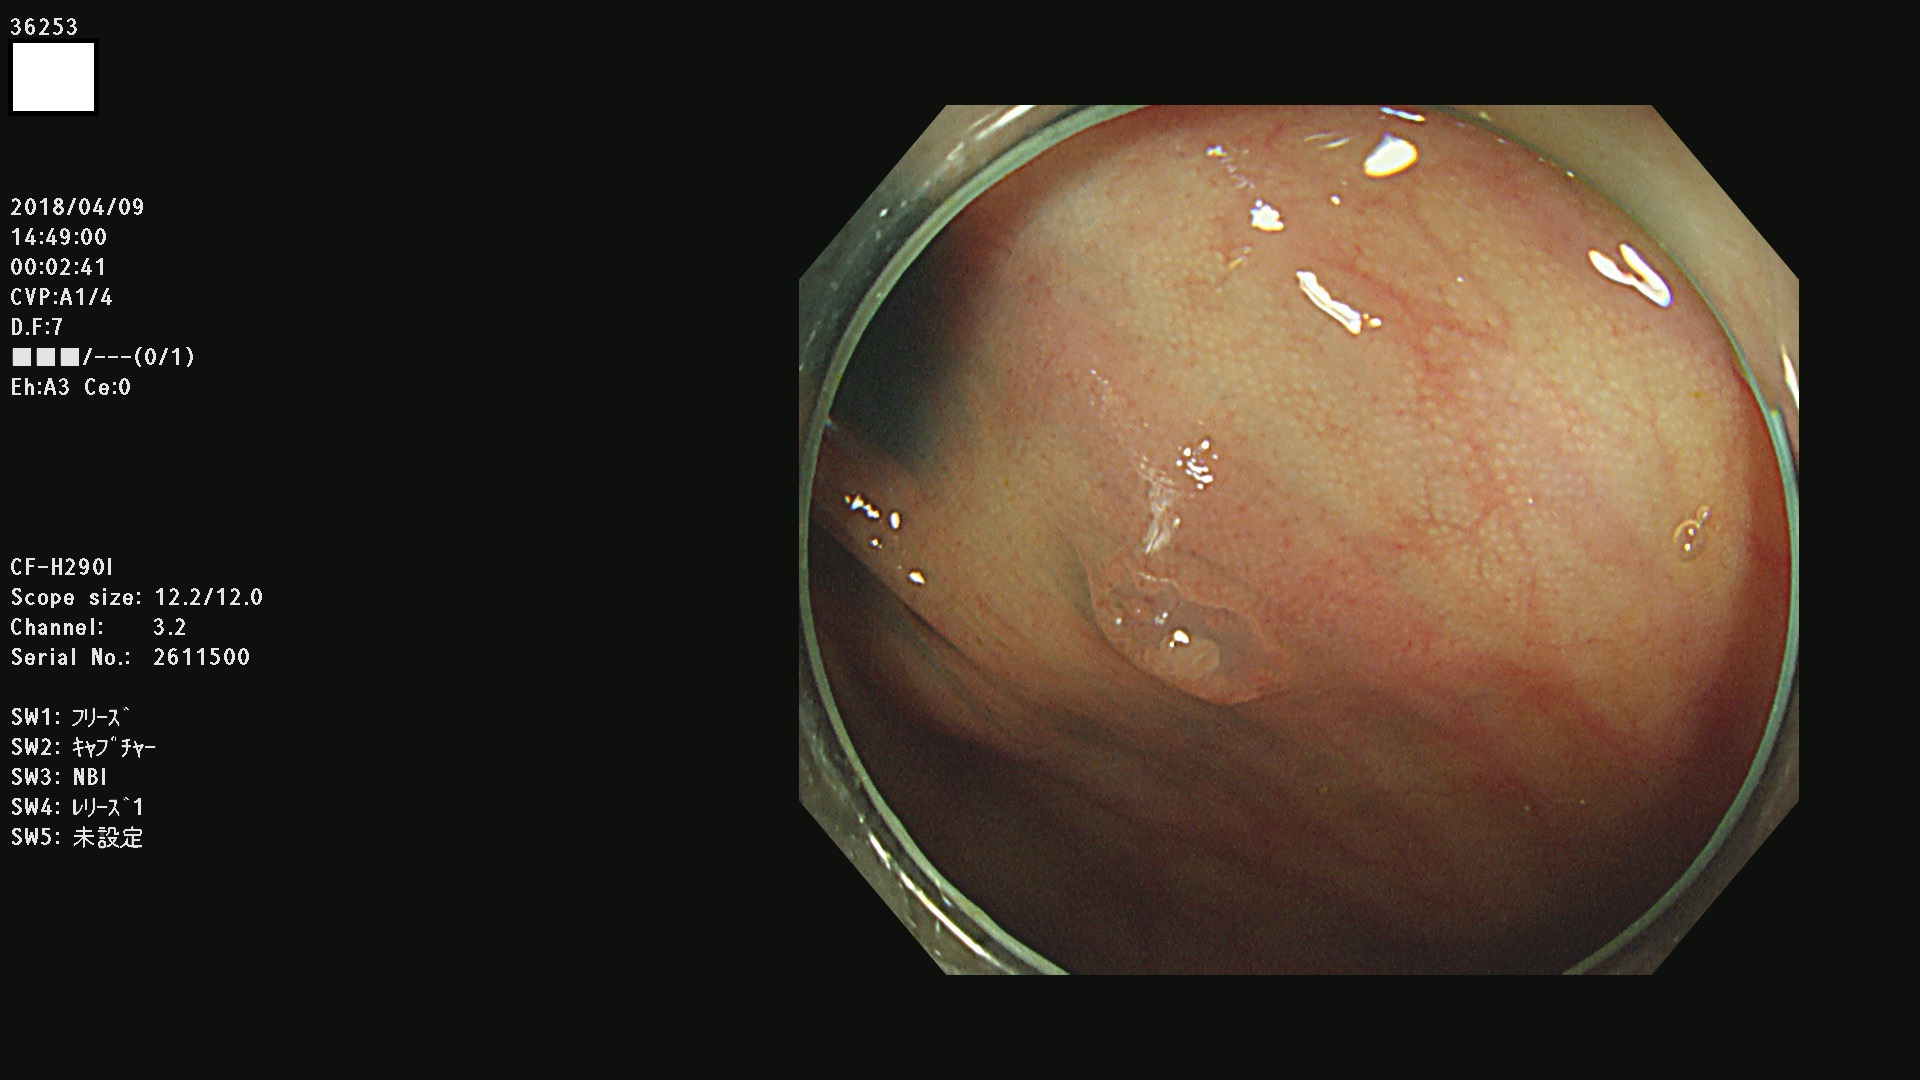

36201 36202 36203 36205 36207 36209 36210 36212 36213 36214 36215 36217 36220 36221 36222 36224 36225 36226 36227 36229 36230 36231 36232 36235 36236 36238 36240 36243 36244 36246 36247(SSAPのみ。SPS) 36248 36249 36251 36252 36253 36254 36255 36256 36257 36258 36259 36261 36262 36264 36265 36267 36269 36270 36272 36274 36275 36276 36279 36280 36281 36283 36285 36288 36289 36291 36292 36295 36296 36297 36299

発見困難で危険性の高い平坦型病変(上記100名より抽出)